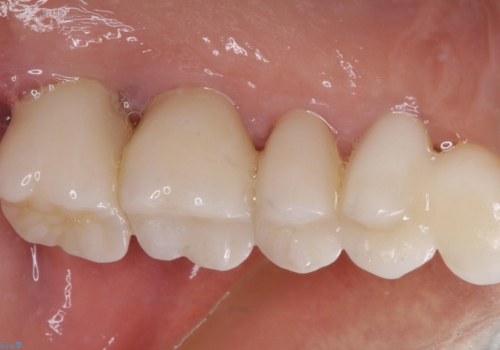

仮歯に置き替え、歯周外科処置(APF、歯肉弁根尖側移動術)による歯周ポケット除去を行った後に、オールセラミッククラウンにて補綴することとしました。

歯周外科処置により歯周ポケットを除去することができ、クラウン装着後はブラッシング時の出血や歯肉の腫れが気にならなくなりました。